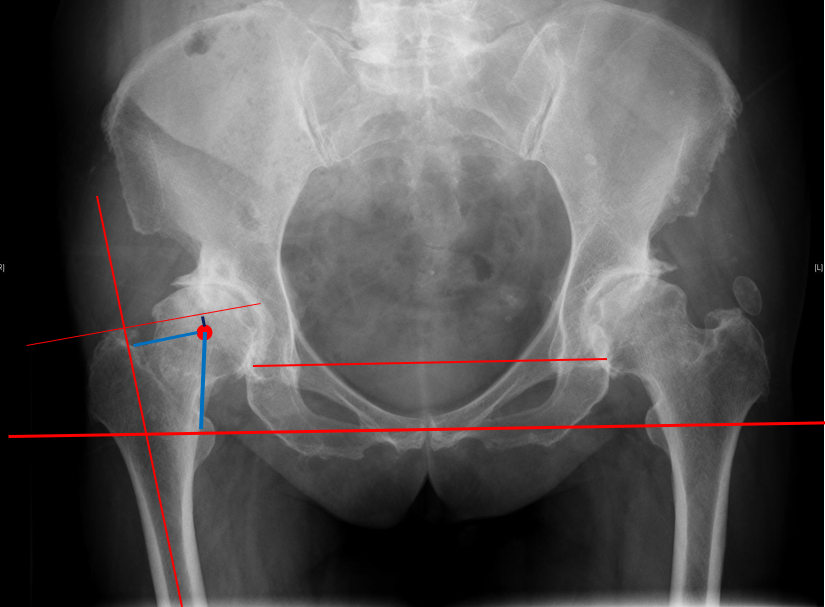

确定正常侧髋关节的旋转中心镜像至患侧:

确定股骨颈截骨线对侧髋关节正常,可以对侧为参照

-定出截骨高度(可以小粗隆为参照)

-镜像确定在患侧的截骨高度

单看股骨侧,大转子顶点和股骨头旋转中心的关系恢复了

但髋臼旋转中心点上移了造成了患肢术后肢体短缩因此如果术中发现髋臼旋转中心点有上移或下移,股骨假体也应相应的吊高或下沉以获得双下肢等长

术后股骨头旋转中心点增高,导致患肢延长